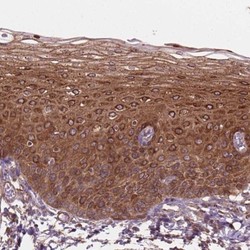

- Immunohistochemistry-Paraffin: FAM115A Antibody [NBP2-48521] - Staining of human esophagus shows strong cytoplasmic positivity in squamous epithelial cells.